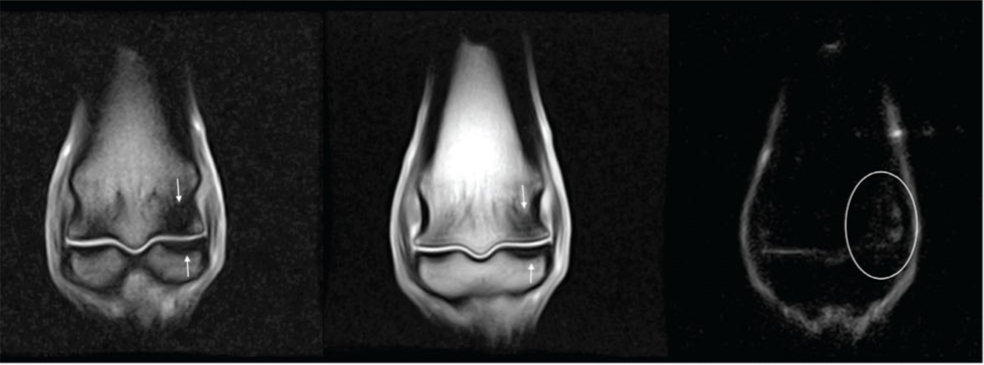

We are seeing such diagnoses more commonly in recent years. I am not sure if this is an increase in the prevalence of the condition, or if as a profession, we are becoming more accurate with our diagnosis with the more common use of advanced imaging techniques such as nuclear scintigraphy, CT (computed tomography) and MRI (magnetic resonance imaging).

First, as I have said before in this column, accurate diagnosis is very important. It is relatively common for lameness that has been localized to the fetlock region to result in normal radiographic and ultrasound examination. We often need to investigate further, with the advanced modalities mentioned above. The term ‘bone bruise’ has gained popularity in recent years and is commonly used to describe a multitude of pathology. The first distinction is the area of bone involved in the fetlock region. We often see injury to the subchondral bone (bone just under the layer of articular cartilage). More specifically, it is also important to characterize the type of bone injury. An acute injury, bone edema is often present without any other changes, ‘edema’ or fluid trapped within the bone, similar to the swelling one may find with a soft tissue injury. In more chronic cases, we observe that the bone changes in density, either by increasing the mineral content (aka sclerosis), or decreasing the mineral content resulting in bone lysis (disintegration).

In some cases, other injures will be seen concurrently with bone injury and we are often concerned with the overlying cartilage when subchondral bone injury is identified. In such cases, therapy directed at associated soft tissues and joints may be indicated.